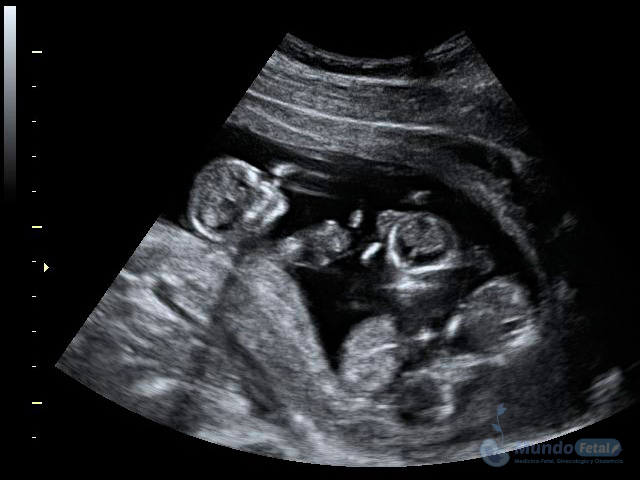

Ultrasonido Embarazo Múltiple

Es esencial detectarlo desde el primer trimestre (especialmente 11-13.6 semanas de gestación) con la intención de conocer el número de bebes, cuántas placentas y bolsas amnióticas, ya que el seguimiento de estos es distinto, esto por los riesgos que conllevan de presentar alguna alteración propia de estos embarazos, indicativos de una vigilancia estrecha y estudios complementarios, durante toda la gestación.